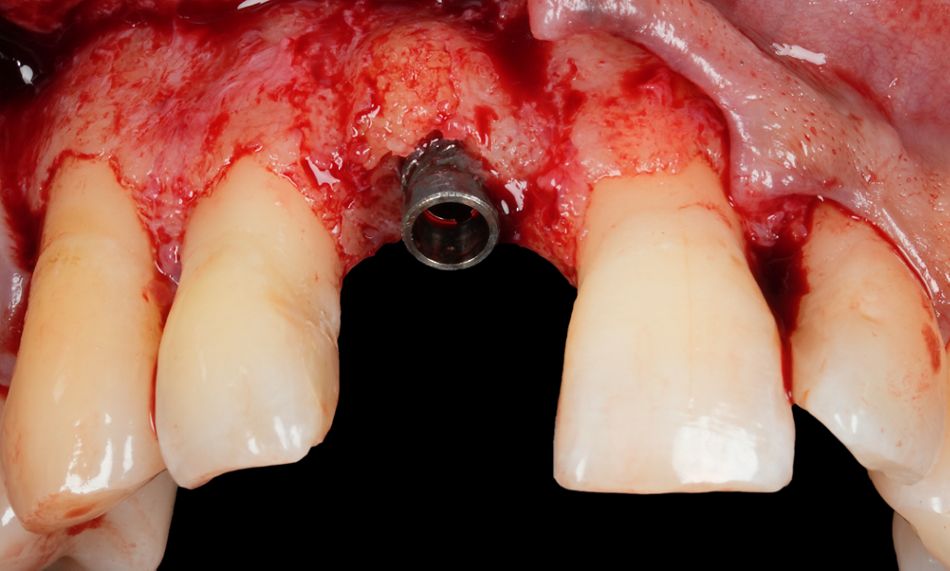

A full-thickness mucoperiosteal flap was elevated to expose the affected implant and the surrounding bone defect. The clinical examination confirmed the presence of a mixed horizontal and crater-like peri-implant bone defect, as previously noted on radiographs (Fig. 9).

Fig. 9

The exposed implant surface was thoroughly decontaminated using the GalvoSurge® Dental Implant Cleaning System. This electrochemical cleaning technique operates by generating hydrogen bubbles at the implant surface, which mechanically lift and detach biofilm and other contaminants without damaging the titanium microstructure. The process allows for an effective and atraumatic surface decontamination, creating a favorable environment for potential re-osseointegration and regenerative healing (Figs. 10-12).

Following decontamination, guided bone regeneration (GBR) was performed to correct the bone defect. A particulate allograft material, botiss maxgraft® plus, was used to fill the defect, providing osteoconductive scaffold properties. The grafted area was then covered with a resorbable collagen membrane,  Jason® membrane, to stabilize the graft material and promote selective cell repopulation while preventing soft tissue invasion into the graft site (Figs. 13,14).